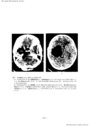

第3脳室近傍腫瘍の神経放射線診断-脳血管撮影を中心に- III 主に第3脳室の側方に発育する腫瘍(2)